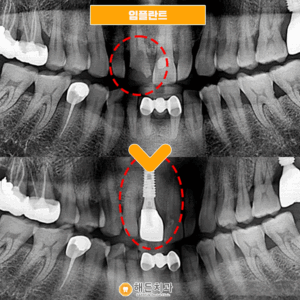

해든치과 임플란트 환자분의 간식선물🥨

안녕하세요~ 해든치과입니다 임플란트 치료분인 환자분께서 치료 전 통증과 불편함이 계속 있었지만 치과에 대한 두려움 때문에 한동안 참고 지내시다가 내원해 주셨습니다 그동안 치과에 대한 기억이 좋지않아 차마 발걸음이 떨어지지 않았는데 막상 치료받아보니 걱정이 무색하게 안아프게잘 치료해주셔서 너무 감사하시다며, 치과 공포증이 다 사라졌다시며 간식을 선물해주셨어요! 예쁘게 생긴 도넛이 맛도 얼마나 좋았는지 ㅠㅠ 더보기…